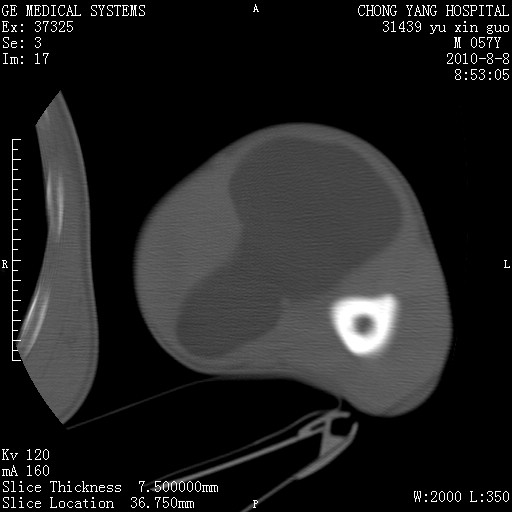

标题: CT28267:M57Y 上臂包块8年余。 [打印本页]

标题: CT28267:M57Y 上臂包块8年余。

包膜光滑、完整的脂肪密度肿块,支持脂肪瘤。